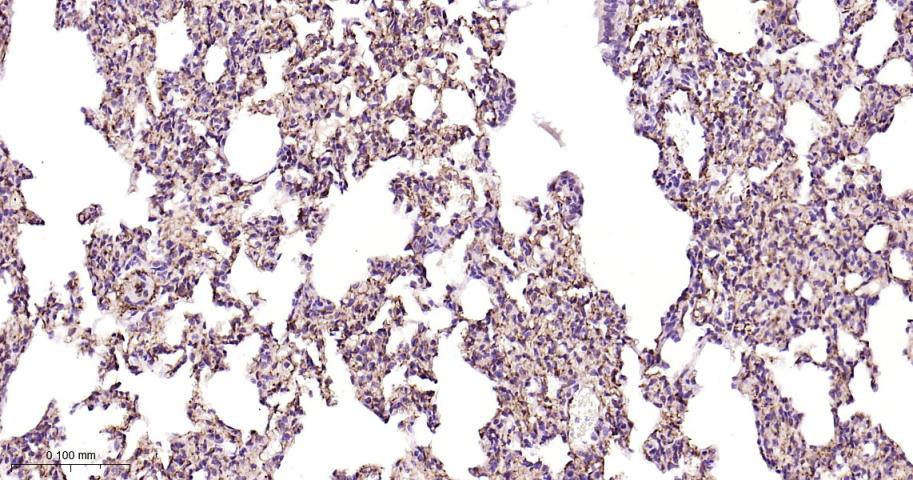

Paraformaldehyde-fixed, paraffin embedded Rat Lung; Antigen retrieval by boiling in sodium citrate buffer (pH6.0) for 15 min; Antibody incubation with CD146 Monoclonal Antibody, Unconjugated(bsm-61136R) at 1:200 overnight at 4°C, followed by conjugation to the bs-0295G-HRP and DAB (C-0010) staining.